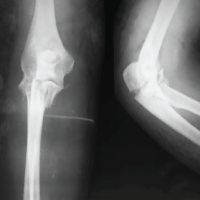

A 12-year-old male patient, student, presented to our outpatient department with complaints of pain in the middle back for the past 6 months which was insidious in onset, gradually progressive, mild to moderate in intensity, non-radiating but associated with night cries. The patient also complained of deformity in the back for a similar duration. On examination, there was tenderness over the dorsal spine, and a scoliotic deformity with convexity toward the left side with a small left-sided rib hump (Fig. 1a and b). Neurological examination was normal except that he had slight upper motor neuron features like extensor plantar response. The power in the bilateral lower limb was 5/5 as per the medical research council grade and sensory was also normal (2/2). Plain radiograph of the whole spine which revealed a scoliotic deformity of dorsal spine with convexity toward the left side with non-visualization of right-sided pedicles of D7 and D8 vertebrae (Fig. 1c). Further, a magnetic resonance imaging (MRI) was done which revealed a destructive lesion (3 × 4 cm) at D7 and D8 vertebra involving the central canal with surrounding soft-tissue extension (Enneking stage 3). It involves zones 10–12 with an extension to layer D as per Weinstein-Boriani-Biagini classification system [5], as illustrated in Fig. 2a-c. Non-contrast computed tomogram (NCCT) of the focal area revealed an expansile lytic lesion of size 3 × 4 cm with calcification involving spinous process, lamina, and pedicles of the right side of D7 and D8 vertebrae suggestive of osteoblastoma (Fig. 2d-f). Blood examinations were normal except for slightly elevated alkaline phosphatase values. The parents were counseled for surgical excision of the tumor and stabilization of segments using pedicle screw fixation. Under neuromonitoring guidance, using a standard posterior midline approach pedicle screw was inserted from D4 to D10 levels in a staggered arrangement. A connecting rod was given on one side for stabilization and open surgical resection of the tumor along with laminectomy and right-sided pedicles were removed at D7 and D8 vertebrae (Fig. 3a). Following excision and decompression, deformity was corrected by cantilever technique. Samples were taken for gross and histopathological examination and the wounds were closed in layers over a drain. The post-operative period was uneventful and the check x-ray was satisfactory (Fig. 3b). He was mobilized the 1st day after surgery (Fig. 3c). Histological report came to be consistent with the pre-operative diagnosis i.e. osteoblastoma (Fig. 4). The patient was followed up at, 4 weeks, 6 months, and 12 months after the surgery. He was doing well with fully active in school and sports activity.